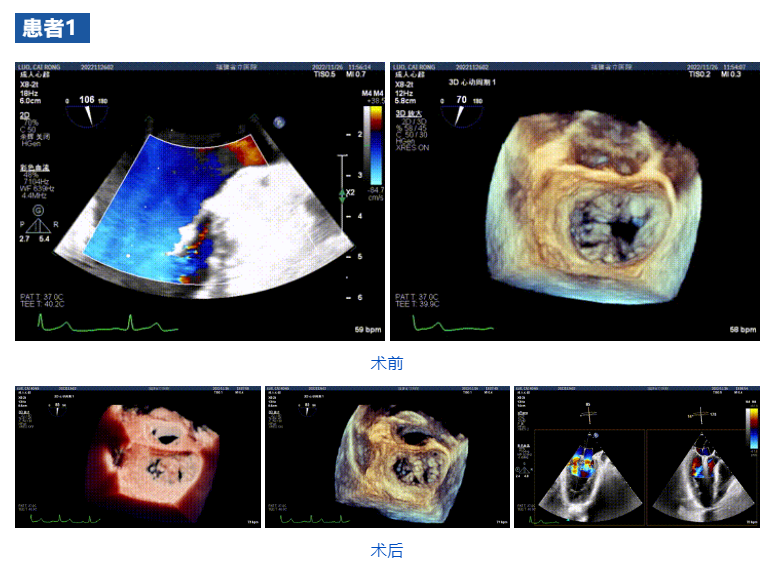

接受治療的三例患者均為器質(zhì)性重度二尖瓣反流(DMR)患者,術(shù)前超聲提示二尖瓣后葉脫垂伴4+反流,左室舒張功能減退。郭延松教授攜同團(tuán)隊(duì)成員陳新敬副教授和洪景宣、方明程、楊清勇主治醫(yī)師、心外科丁杭主任以及超聲科賴寶春、葉振盛主治醫(yī)師共同進(jìn)行病情討論??紤]到患者高齡、基礎(chǔ)疾病多、STS評分高,為外科手術(shù)極高危患者,不適合進(jìn)行外科開胸二尖瓣手術(shù),因此決定為患者實(shí)施經(jīng)導(dǎo)管緣對緣修復(fù)介入術(shù)(JensClip經(jīng)導(dǎo)管瓣膜夾系統(tǒng))。

在浙江大學(xué)醫(yī)學(xué)院附屬第二醫(yī)院王建安教授團(tuán)隊(duì)的支持下,手術(shù)經(jīng)股靜脈-房間隔入路,采用全身麻醉插管,在TEE和DSA引導(dǎo)下完成房間隔穿刺。置入JensClip瓣膜夾系統(tǒng)后,在左房調(diào)整瓣膜夾的位置和軸向,后進(jìn)入左室,在TEE引導(dǎo)下捕捉二尖瓣前后瓣葉,并關(guān)閉瓣膜夾。經(jīng)TEE反復(fù)確認(rèn)手術(shù)效果后最終鎖定并釋放瓣膜夾。術(shù)后即刻超聲顯示瓣膜夾位置穩(wěn)定,功能良好,二尖瓣反流由術(shù)前4+減少至微量,手術(shù)圓滿成功。